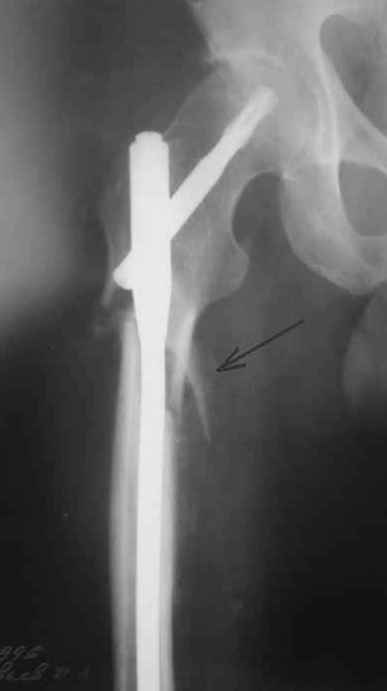

небольшое замечание по поводу бедра - сразу не рассмотрел - гвоздь обязательно надо было заблокировать дистально и крайне желательно -и проксимально тоже. Без блокирования не исключена ( хоть и не очень вероятна) ротация фрагментов.

Вроде ж Fixion не блокируется?

Уупс -моя ошибка, я не знал, что fixion - это expandable nail. Вопрос снят. Спасибо

Да нет, вопрос уместный. Тут перелом ниже истмуса, и в дистальном отломке винты были бы не лишние. И ретроградный Fixion с винтами есть.

На операции я оставил осколок в области приводящих мышц бедра (ни пальпаторно, ни спицей сдвинуть не смог, "заклинило" насмерть). Фото спустя 2 месяца после операции (PFN).

Только сейчас пациент стал более или менее активным. Сразу после операции жалобы на сильные боли при отведении и приведении бедра в области отломка. Сейчас отломок пальпируется и пациент испытывает дискомфорт, хотя амплитуда движений объективно прогрессирует.

Теперь думаю, надо все-таки было через минидоступ или резецировать, либо репонировать. Обычно при таких операциях уже на 2-й день пациенты на костыли и по отделению, а у этого задержка длительная получилась. Только спустя 2 недели кое-как на костыли взобрался. Ни отека, никакой неврологии, только эти боли в области осколка.